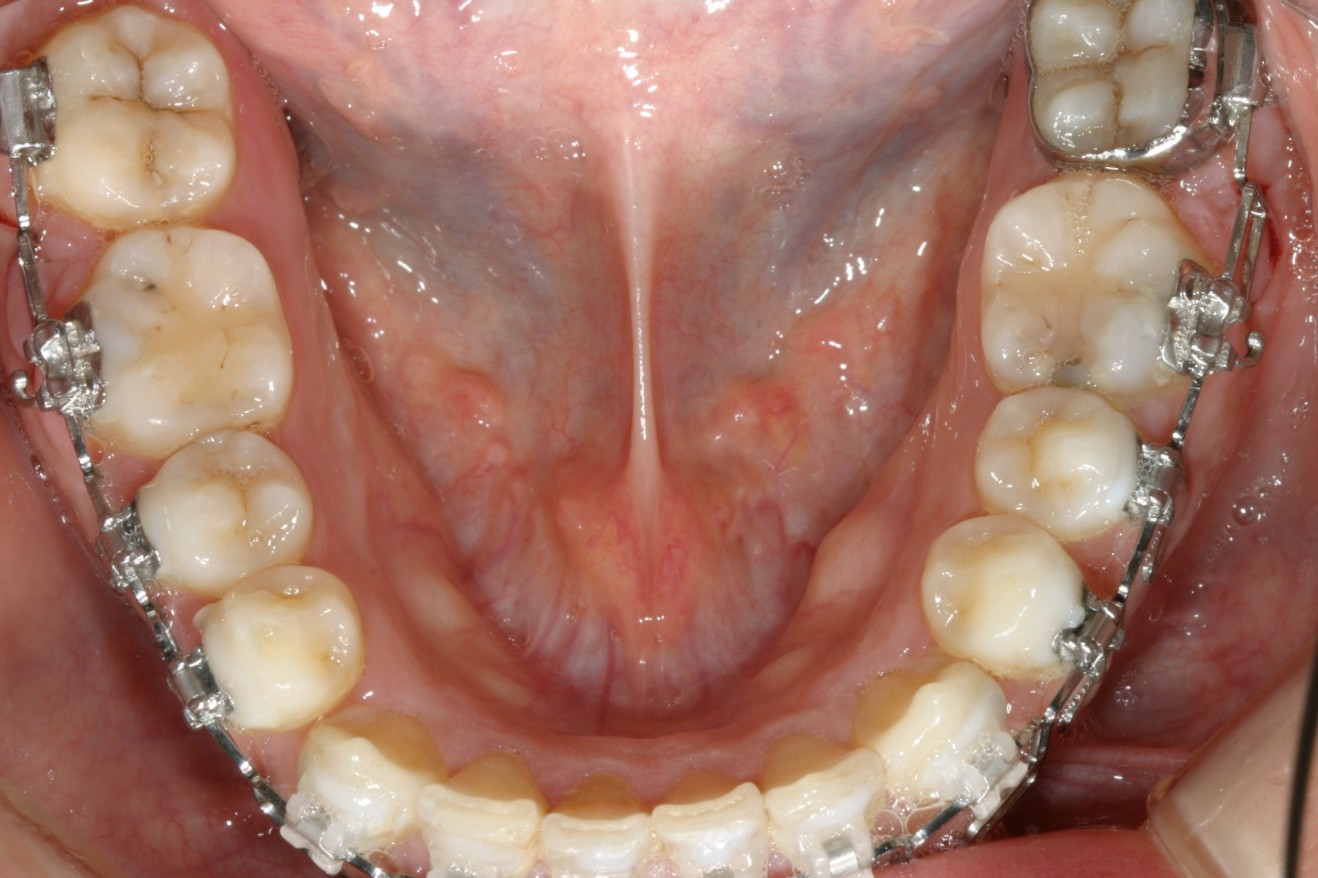

この様に綺麗に改善致しました。

下顎もこんな感じです。綺麗でしょ?